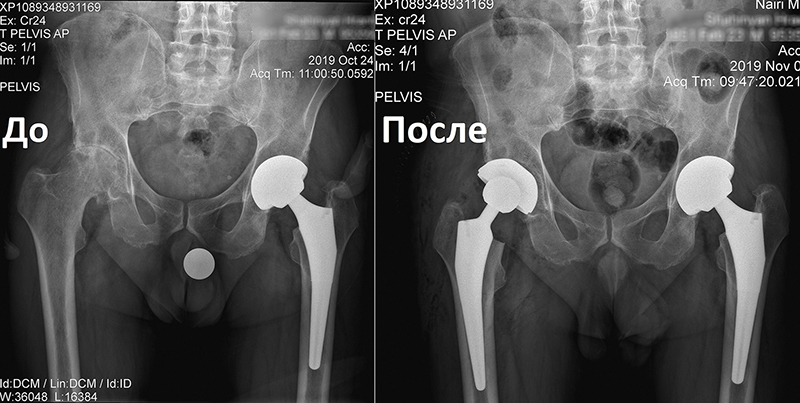

«Նաիրի» բժշկական կենտրոն էր դիմել 1951 թ. ծնված տղամարդ՝ երկկողմանի անգիլիզացնող կոքսարթրոզով, առաջին աստիճանի ճարպակալումով: Պացիենտը գանգատվում էր մշտական ցավերից, շարժումների խիստ սահմանափակումից, քայլելու դժվարությունից՝ անգամ հենակների օգնությամբ:

Որոշում կայացվեց իրականացնել փուլային երկու վիրահատություն: Առաջինը վիրահատվեց ձախ ոտքը, քանի որ այդ վերջույթում ձևախախտումն առավել արտահայտված էր:

Երկու ամիս անց, երբ պացիենտը սկսեց քայլել առանց հենակների, վիրահատվեց նաև աջ ոտքը:

Երկրորդ վիրահատությունից 6 շաբաթ անց պացիենտը ցավեր չունի և քայլում է առանց հենակների, ապրում լիարժեք կյանքով: